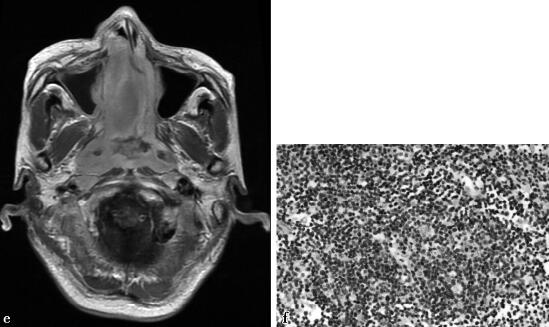

病例2-1-4:CT、MRI平扫及增强扫描。

图1a~b,分别为平扫CT、增强CT。双侧鼻腔内不规则软组织密度肿块影,向前侵及鼻前庭、鼻翼;鼻中隔、中下鼻甲及双侧上颌窦内侧壁骨质破坏;向后累及鼻咽后壁。增强扫描病灶轻-中度强化(CT值由43HU升至59HU)。图1c~f,分别为双侧鼻腔内肿物呈近似等T1、T2信号,病灶向前侵及鼻前庭、鼻翼。向后累及鼻咽后壁及双侧咽旁间隙。向右突入至上颌窦内、累及眶内壁。向左挤压左侧上颌窦内侧壁。增强扫描病灶轻-中度强化。图1f,病理证实为鼻腔NK/T细胞淋巴瘤。

病例2-1-4,鼻腔NK/T细胞淋巴瘤。